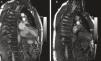

O ecocardiograma transtorácico (ETT) pré-alta, realizado após seis semanas de antibioterapia com meropenem e vancomicina, revelou um volumoso aneurisma micótico do segmento basal da parede inferior do VE junto ao anel mitral posterior (Figura 1), diagnóstico confirmado por RMN cardíaca (RMC) (Figura 2A). Muito embora a morfologia do aneurisma não sugerisse etiologia isquémica, foi realizada coronariografia que confirmou a normalidade das artérias coronárias epicárdicas.

AO – Aorta torácica descendente, LA – Aurícula Esquerda, LV – Ventrículo Esquerdo.